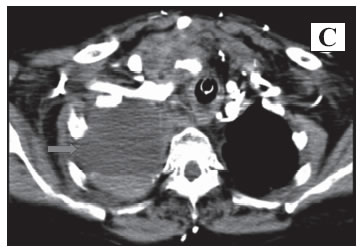

Mujer de 54 años quien ingresó con choque hipovolémico y séptico de origen abdominal requiriendo paso de catéter subclavio derecho para la administración de cristaloides e inotrópicos; la radiografía de tórax luego del procedimiento (Pánel A) mostró opacidad del hemitórax superior derecho con borde bien definido (Flecha), engrosamiento apical superior y mínima cantidad de líquido en el ángulo costofrénico ipsilateral, insinuando la presencia de hemotórax; por la condición clínica se realizó seguimiento clínico y radiológico. La paciente presentó mejoría, por lo que se retiró el catéter presentando nuevamente compromiso hemodinámico sugiriendo lesión vascular siendo necesario nueva radiografía de tórax (Pánel B) que mostró extensión de la lesión descrita (Flecha) y angioTAC (Pánel C) que evidenció hematoma en cuello y hemotórax derecho sin extravasación de líquido, aunque no se descartó lesión arterial (Flecha). La paciente presentó deterioro clínico y falleció antes de poder realizarse una intervención quirúrgica.

Este caso ilustra que el paso de catéter central en personal experimentado tiene complicaciones del 1-3% y cuando se sospecha lesión vascular, el retiro del catéter empeora el cuadro.